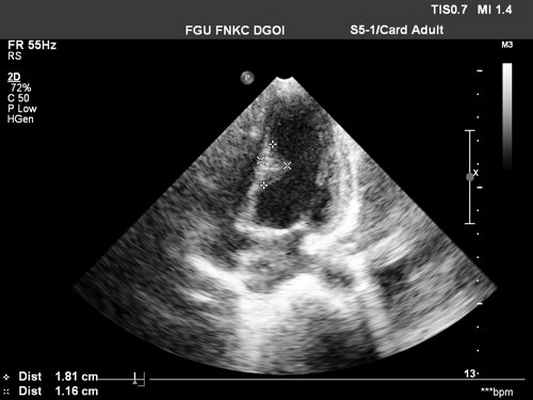

- Уменьшение EF наклона передней митральной створки, если миксома пролабирует в левый желудочек (рис.155).

Миксома левого

предсердия: плотный

эхосигнал между

створками

митрального клапана

в диастолу.

1 тип -небольшие пролабирующие миксомы. Эти мобильные левопредсердные миксомы пролабируют в митральный клапан во время диастолы, не нарушая движения клапана. Диастолическое облако сигналов между створками митрального клапана в этом случае является единственным показателем при одномерной эхокардиографии.